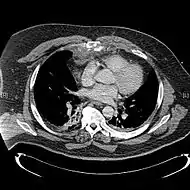

Сверху: грудина окрашена цветом морской волны. Внизу: компьютерная томограмма оскольчатого перелома грудины.[1] | |